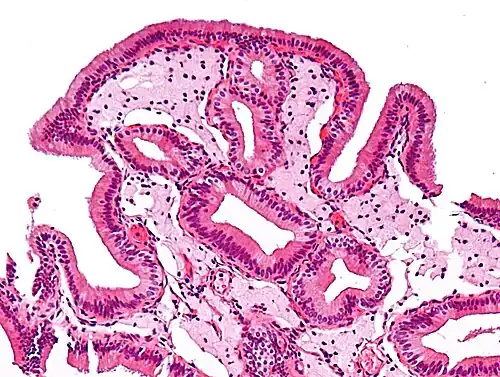

Micrograph of cholesterolosis of the gallbladder -